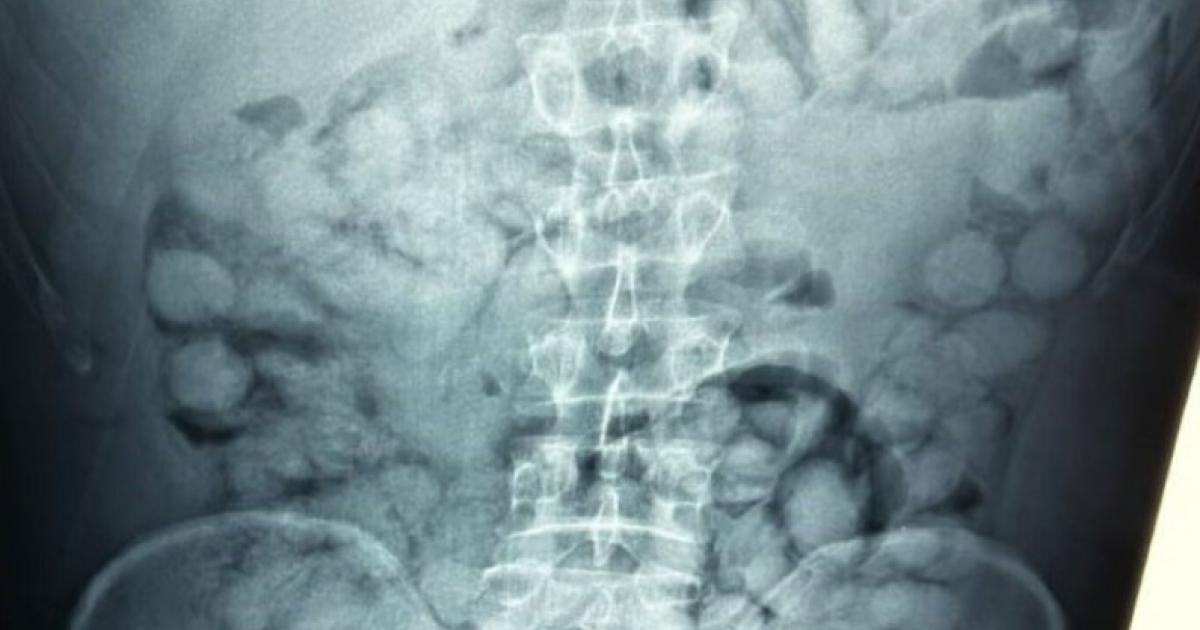

Ένας άνδρας, από τη Βραζιλία, συνελήφθη το πρωί στο αεροδρόμιο «Ελευθέριος Βενιζέλος», κατηγορούμενος ότι είχε καταπιεί σημαντική ποσότητα κοκαΐνης.

Σύμφωνα με την Αστυνομία, ο άνδρας έφτασε στην Αθήνα, μέσω Παρισιού και στον έλεγχο που διενεργήθηκε, διαπιστώθηκε ότι είχε καταπιεί περίπου 100 συσκευασίες κοκαΐνης.